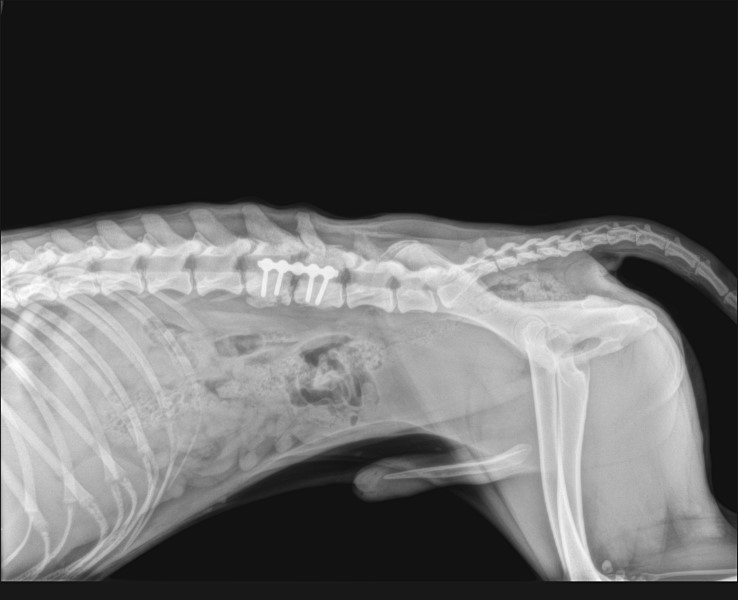

Opéré à la FBM en mars 2023 d’une fracture des vertèbres . + d’infos à venir